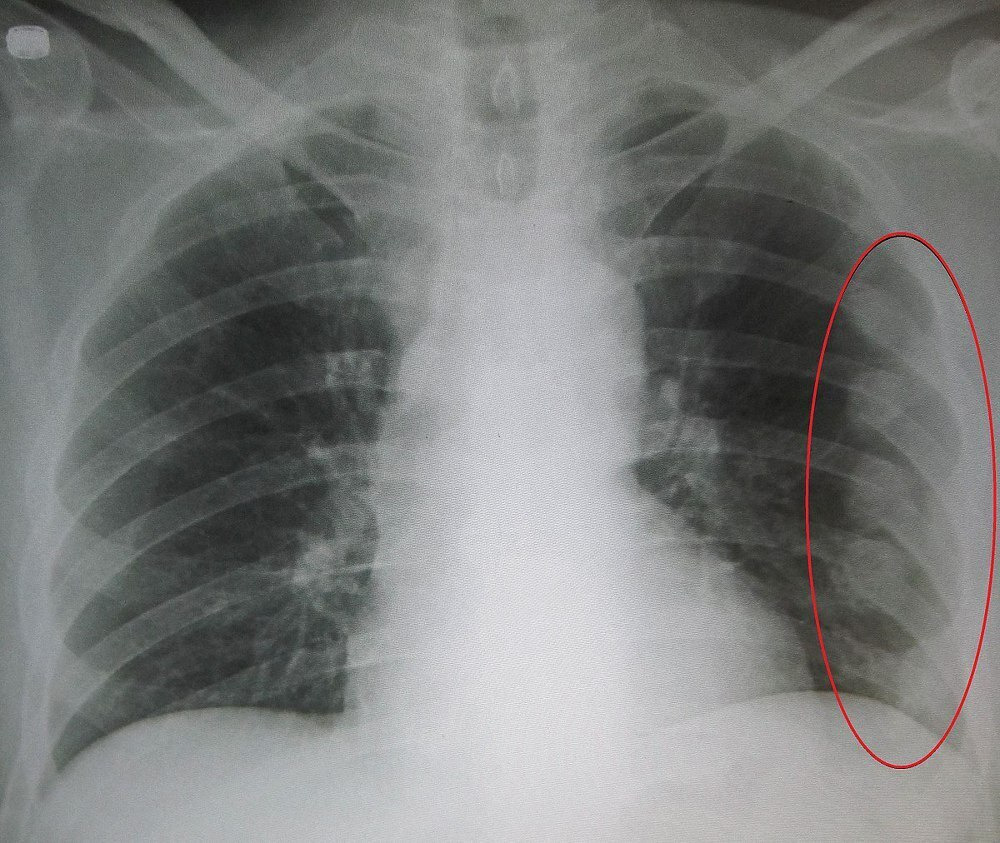

갈비뼈 손상은 호흡 시마다 갈비뼈가 움직이기 때문에 통증을 유발하여 호흡을 얕게 만듭니다. 이로 인해 산소 부족을 경험할 수도 있으며, 심각한 경우 폐에 손상이 생길 가능성도 있습니다. 심각한 호흡 곤란이 발생하면 반드시 응급실을 방문하여 폐 손상 여부를 확인해야 합니다.

호흡 곤란은 종종 숨이 차거나 심장 박동이 빨라지는 증상과 함께 나타날 수 있습니다. 이 경우 적절한 산소 공급이 필수적이며, 지속적인 증상 관찰과 전문적인 치료가 필요합니다.

갈비뼈가 단순히 금이 갔다면 회복 기간이 짧을 수 있지만, 완전히 부러졌거나 주변 장기 손상이 동반된 경우 더 긴 치료와 회복이 필요합니다. 갈비뼈 부상이 폐, 간과 같은 주요 장기에 영향을 미친다면 회복 속도와 방법이 크게 달라질 수 있습니다.